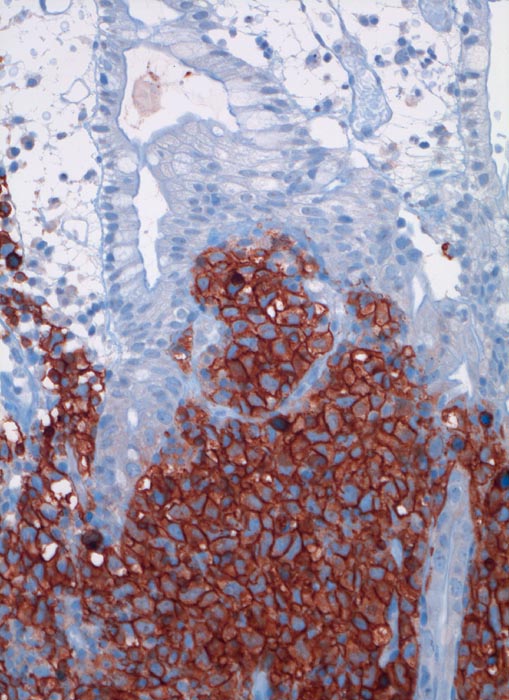

PathoPic ID 3464 - extranodales diffuses grosszelliges B-Zell Lymphom (WHO)

extranodales diffuses grosszelliges B-Zell Lymphom (WHO)

Die CD20 positiven Lymphomzellen infiltrieren die Mukosa.

Immunhistochemie: CD20 positiv, CD3 und CD30 negativ, CD117 negativ

Akute Peritonitis bei Darmperforation

Histologie

Immunhistochemie

CD20 (L26)

200